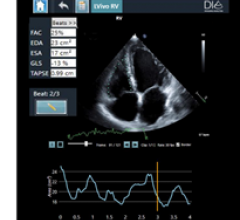

October 29. 2020 — DiA Imaging Analysis announced today that it has received 510(k) clearance from the U.S. Food and ...

October 28, 2020 — Northwestern Memorial Hospital is the first hospital in the United States to purchase Caption Health ...

GE Healthcare is highlighting artificial intelligence (AI) automation features on its Voluson Swift ultrasound platform ...